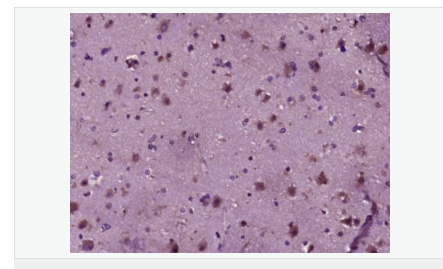

| 產品應用 | ELISA=1:5000-10000 IHC-P=1:100-500 (石蠟切片需做抗原修復) not yet tested in other applications. optimal dilutions/concentrations should be determined by the end user. |